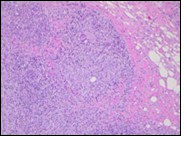

Figure 3.Granulomatous mastitis with scattered langhans and foreign body giant cells, epitheloid cell granuloma and lymphoid ingress11.

Core needle biopsy of idiopathic granulomatous mastitis enunciates multiple aggregates of non- caseating epitheloid cell granulomas within and encompassing breast lobules, constituted of epitheloid histiocytes, lymphocytes, neutrophils and multinucleated giant cells. Granulomatous inflammation is predominantly lobulo-centric. The inflammation is preponderantly composed of lymphocytes, plasma cells, epitheloid histiocytes, multinucleated giant cells and neutrophils. Neutrophils can configure micro-abscesses and encompass vacant micro-cystic cavities, morphological features which are in common with cystic neutrophilic granulomatous mastitis. Non specific lobulitis along with a lymphoid and plasma cell infiltrate accompanies the granulomatous inflammation. Necrosis is usually absent. Neutrophilic micro-abscesses can be accompanied by fistula formation 4, 5.

Multinucleated giant cells are detected in an estimated three fourths (78.5%) instances. Plasma cells are discernible in around half (53.9%) of the subjects and usually appear at the margins of cystic vacuoles with centric accumulation of neutrophils within the granulomas.